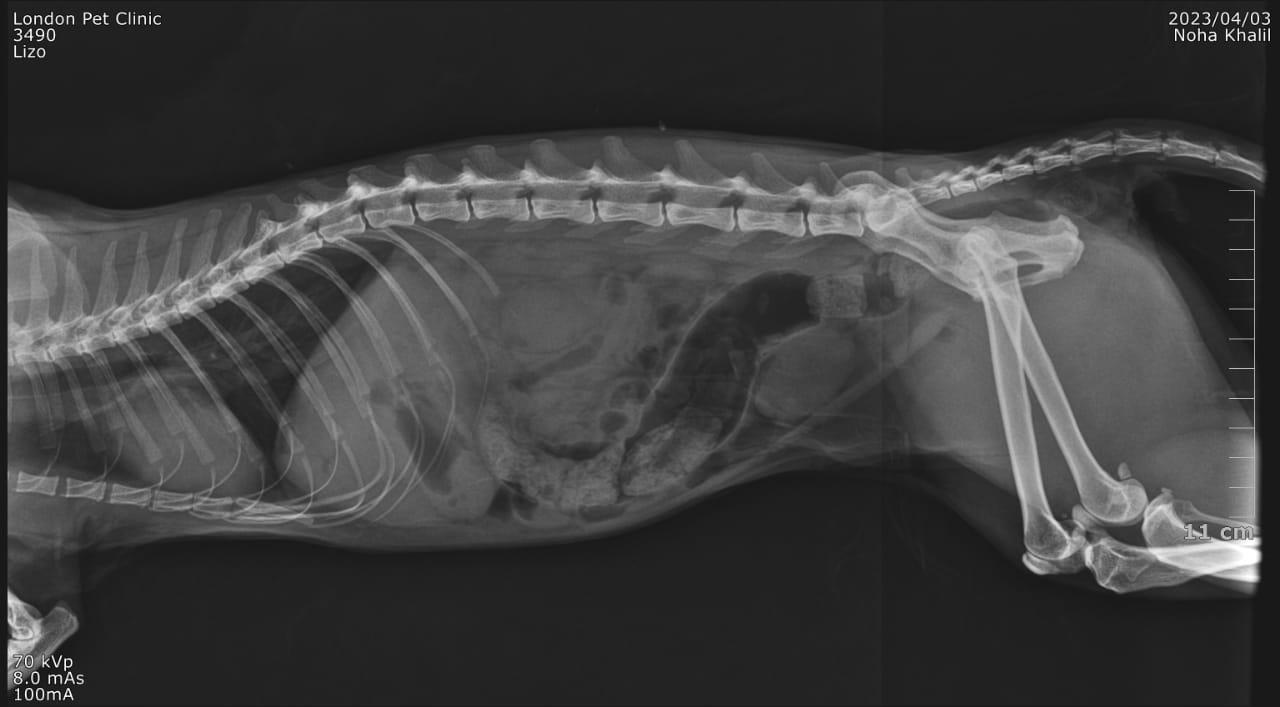

Post operative x ray